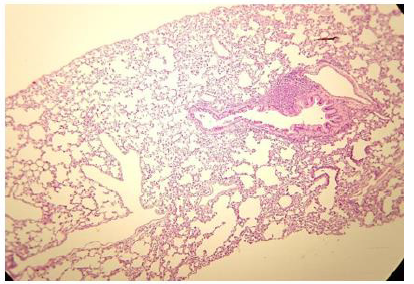

Figure 2: Histologic lung section, Wistar rat. Dyed with Hematoxylin and Eosin. The 100 X magnification allows to glimpse the very thin membrane (1 μm) that delimits the alveolar gas space from the blood capillaries lung compartments.

The pulmonary vascular tree begins as the main pulmonary artery and repeatedly bifurcates (fractal-like) into arterioles and capillaries that cover 85-95% of the alveolar surface. An exceptionally thin membrane of only 1μm [4] separates the alveolar gas and blood compartments, allowing gases to diffuse rapidly between them (Figure 2).